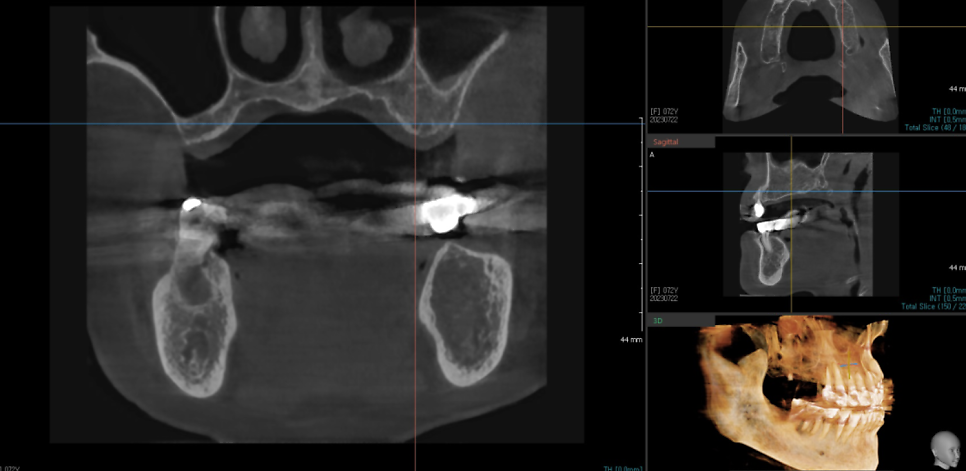

바르디 치과에서는 3d ct 장비를 통해

체계적인 분석이 가능합니다.

내비게이션 임플란트 장비를 적극 활용합니다.

우리가 길을 찾을 때 내비게이션을 활용하듯

디지털 임플란트 기술을 사용하면

정확한 예측이 가능합니다.

수술 시 수술 전, 중, 후

3번에 걸쳐서 촬영하는데요~